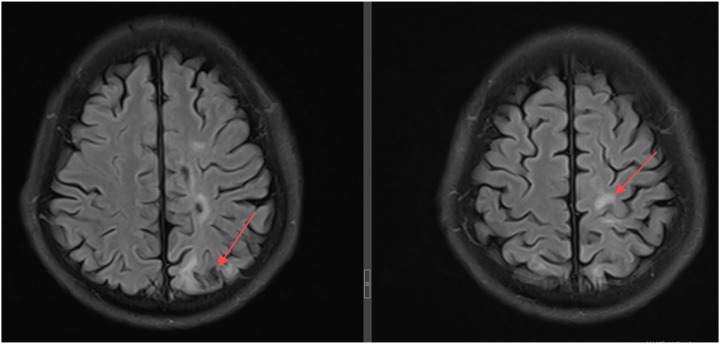

Disseminated TB with central nervous system involvement.

弥散性结核伴中枢神经系统受累。